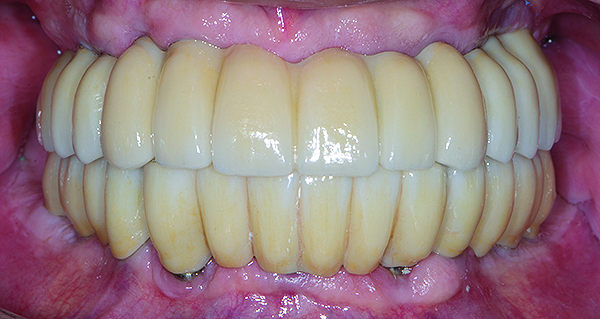

The maxillary prototype was adjusted, polished, and left to function with the mandibular provisional. The definitive maxillary zirconia restoration was then completed from the information provided by the prototype, and the cutbacks for the facial porcelain (Nos. 6 through 11) were done after milling but before sintering. Subsequently, the mandibular prototype was adjusted to the sintered and colored maxillary zirconia framework before the application of porcelain to Nos. 6 through 11 and final glazing (Figure 11). Following this step, the mandibular definitive monolithic zirconia restoration was milled, colored, and sintered. The facial porcelain (Nos. 6 through 11) was applied, and then both maxillary and mandibular restorations were stained and glazed (Figure 12). Both bridges were inserted at the same time (Figure 13 through Figure 15). Minor occlusal adjustments and oral hygiene access was verified and the zirconia surfaces polished. The bridge screws were torqued to 20 Ncm according to the manufacturer’s recommendation, and No. 24 was luted with a provisional cement. Postoperative radiographs were taken (Figure 16).

Fig 15. Intraoral frontal view of completed maxillary and mandibular zirconia restorations.

Figure 15